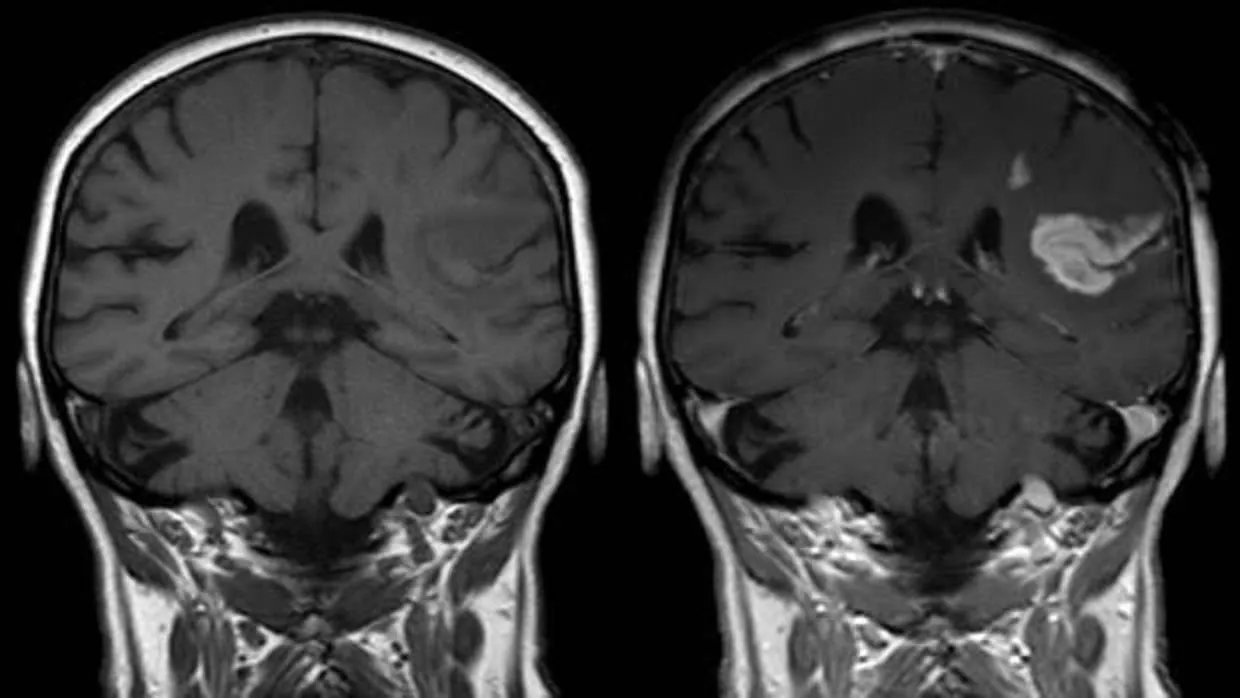

Cada año, más de 17 millones de personas de todo el mundo y cerca de 120.000 españoles padecen un ictus o accidente cerebrovascular , esto es, una disminución u obstrucción del flujo sanguíneo cerebral –ictus isquémico, otrora denominado ‘infarto cerebral’– o una hemorragia por la rotura de un vaso sanguíneo en el cerebro –ictus hemorrágico, anteriormente conocido como ‘derrame cerebral’–. Un episodio cerebrovascular que a día de hoy se corresponde con una de las primeras causas de mortalidad y discapacidad en todo el planeta y que, tal y como han constatado infinidad de estudios, se encuentra fuertemente asociado con la hipertensión arterial y con el colesterol elevado. Entonces, ¿puede esperarse que la combinación de fármacos para bajar las cifras de presión sanguínea y de colesterol disminuya el riesgo de sufrir un ictus? Pues sí. De hecho, un estudio llevado a cabo por investigadores de la Universidad McMaster en Toronto (Canadá) muestra que las personas que toman antihipertensivos y estatinas tienen una probabilidad hasta un 44% inferior de padecer un primer ictus.

Cada año, los ictus son responsables de más de 6 millones de decesos en todo el mundo y de que hasta 5 millones de supervivientes padezcan una discapacidad permanente . Y es que el 30% de las personas que sufre un accidente cerebrovascular fallece a consecuencia del mismo y un 40% adquiere una discapacidad grave. De ahí la importancia, capital, de tomar medidas para reducir el riesgo de estos episodios, lo que se consigue con la toma de fármacos para reducir la presión arterial. Y asimismo, con los fármacos para bajar el colesterol. Pero, ¿qué pasa cuando se toman ambos fármacos a la vez?